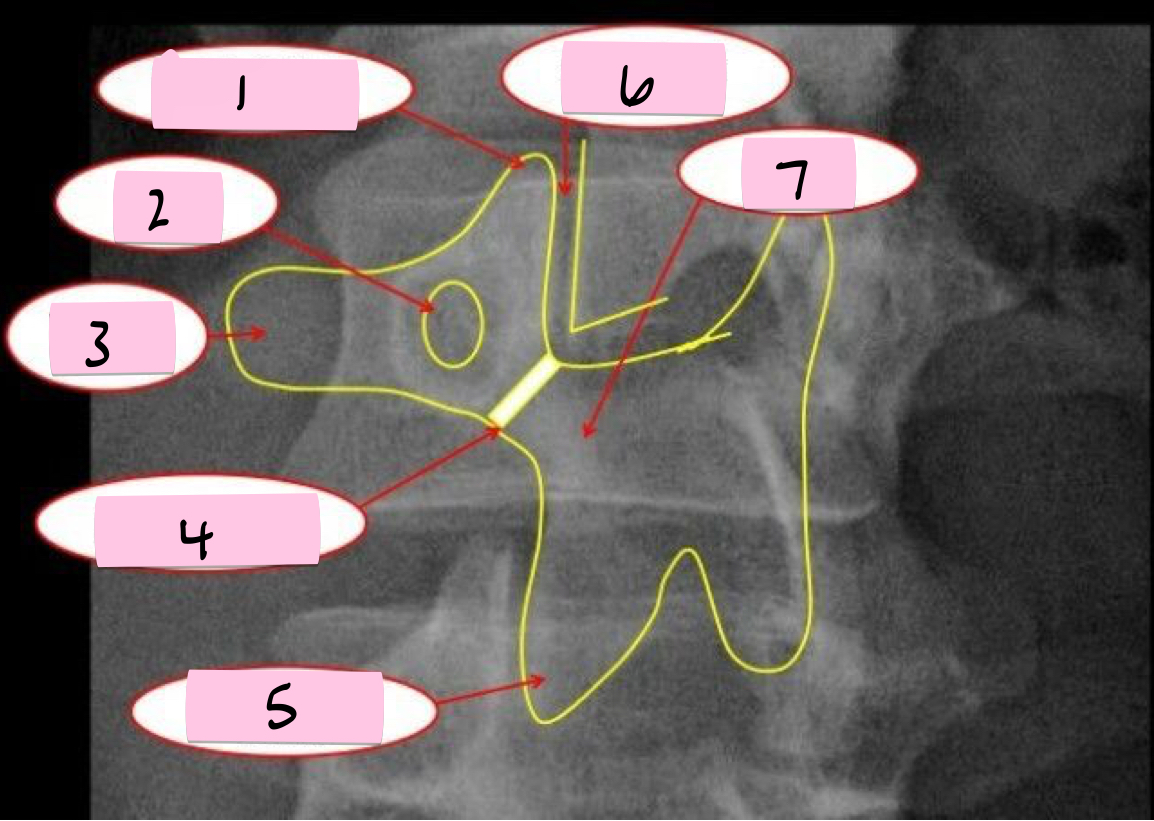

What is 1 pointing to?

Superior articular process

What is 2 pointing to?

Zygapophyseal joint

What is 3 pointing to?

Transverse process

What is 4 pointing to?

Pars interarticularis

What is 5 pointing to?

Inferior articular process

What is 6 pointing to?

Pedicle

What is 7 pointing to?

Scotty dog